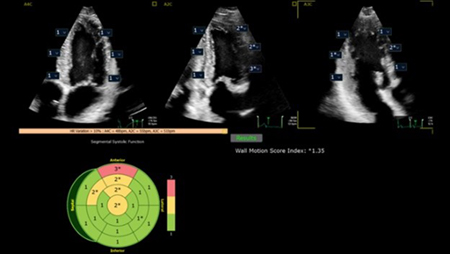

4. 循環器領域のAI*機能を継承

冠動脈疾患を含む様々な心疾患の左室機能評価では,ストレインや局所壁運動異常などの評価をユーザー間のばらつきなく実施することが求められている。EPIQ Elite Elevateには,循環器向け超音波診断装置EPIQ/Affiniti CVx TranscendシリーズのAI*技術が搭載され,自動化による検査の効率化,複雑な解析の客観的評価をサポートする。さらに,新しい細径3D経食道トランスジューサX11-4tも搭載され,SHD領域での活用が期待される。

Auto Segmental Wall Motion Scoring(Auto SWM)